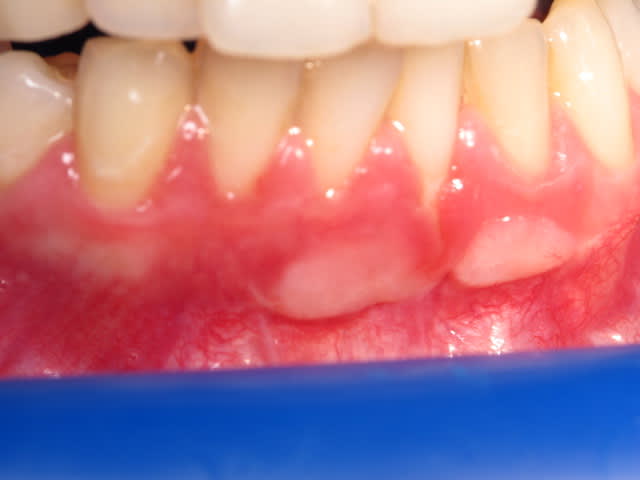

Bonjour à tous, une patiente en fin de premier trimestre de grossesse est venue me consulter pour des "taches " sur sa gencive vestibulaire en regard de son bloc incisif mandibulaire.

Elle me dit avoir subi une greffe gingivale il y a trois ans mais que cette zone vient d'apparaitre.

C'est indolore et asymptomatique on a l'impression que cela correspond au greffon mais pourquoi une modification trois ans après?

Avec la grosesse la gencive est un peu plus inflamée et rouge, le geffon plus epais a moins changé de couleur et par contrast est plus visible.